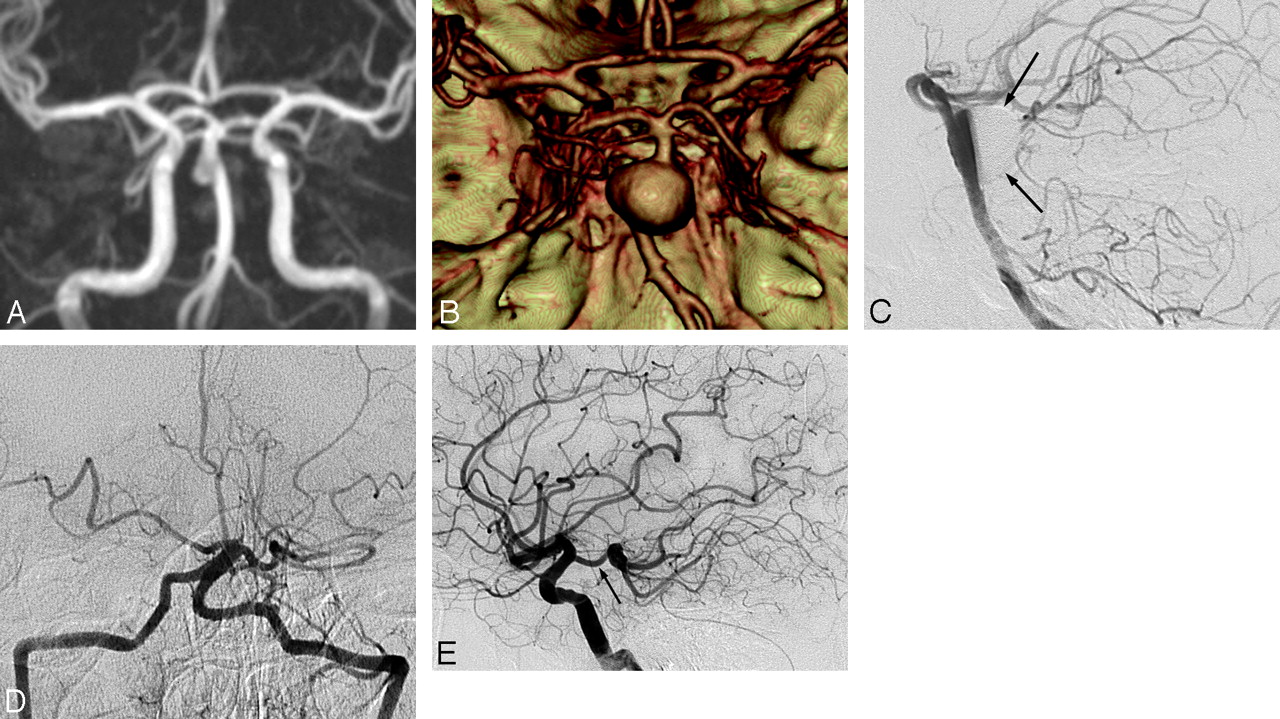

All of the 10 surviving patients treated with the endovascular method underwent follow-up conventional angiography at a mean of 9 months (range, 3–18 months). In 8 of these 10 patients, follow-up angiograms revealed complete resolution of the dilation or stenosis with reconstruction of the basilar artery. In 1 patient who was treated by double stents with coiling for a ruptured basilar artery dissection, a 9-month follow-up angiogram revealed minimal contrast media filling outside the stent (Fig 3). In the other patient who was treated by double-stent placement, a 4-month follow-up angiogram revealed in-stent occlusion of the basilar artery and a hypertrophied right posterior communicating artery that sufficiently supplied the upper basilar artery and its branches (Fig 2). This patient did not have any ischemic complications and completely recovered.

A 48-year-old woman presenting with a subarachnoid hemorrhage. A, Initial vertebral angiogram reveals focal asymmetric dilation of the basilar artery. B, Minimal contrast media filling remains in the coil-embolized pseudoaneurysmal sac outside the stents. C, A 9-month follow-up angiogram shows complete obliteration of the pseudoaneurysmal sac and minimal contrast media filling portion in the right side outside the stents. Note the gap (arrow) between the stents and contrast media filling portion.